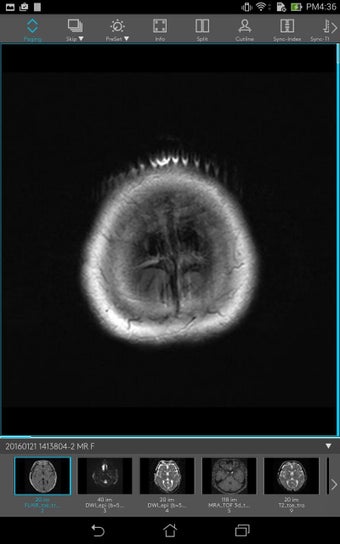

Untuk memberikan perawatan terbaik bagi pasien, para profesional kesehatan perlu memiliki akses cepat dan mudah ke riwayat medis pasien, termasuk data laboratorium, resep obat, dan laporan radiologi. Dengan Join, mereka dapat dengan mudah mengirimkan gambar rekam medis pasien kepada rekan mereka, sehingga mereka dapat dengan cepat dan efisien membuat diagnosis dan rencana perawatan.